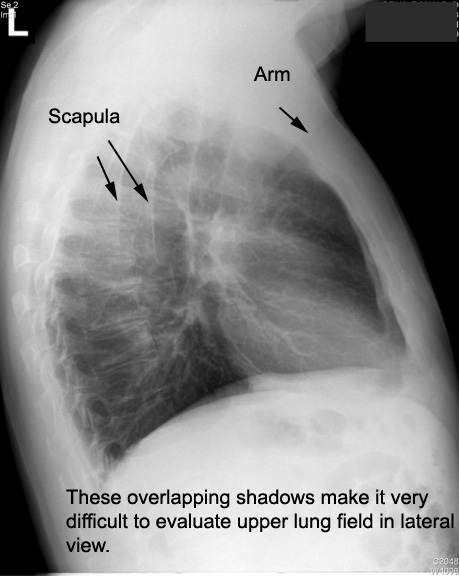

| CXR | Identify axillary fold and Scapula | Answer | |